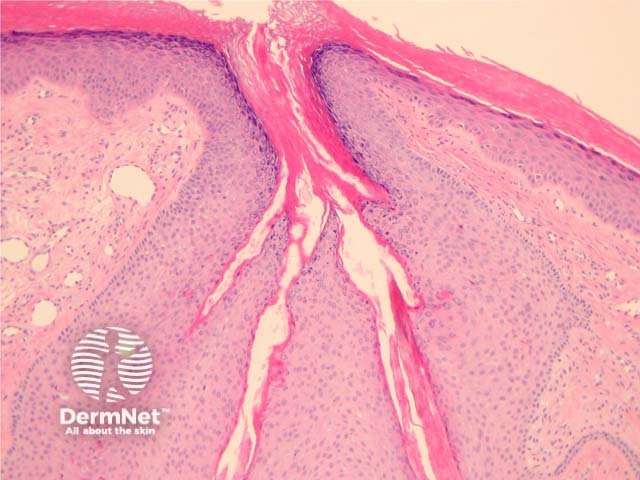

In trichofolliculoma, sections show numerous small follicles radiating from a central larger follicle. The hairs are surrounded by a well circumscribed dense stroma. (figures 1–3). The surrounding hairs are generally very small (vellus). Intermixed Merkel cells and sebocytes may be seen. A sebaceous variant has been described (sebaceous trichofolliculoma).

As with all follicular tumours, there may be numerous mitoses/apoptotic figures within basaloid cell nests which are contributing to the production of a hair shaft – these should not be confused with a proliferating malignant process.

Figure 2